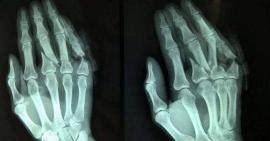

Triệu chứng gãy xương bàn tay bạn cần biết

Gãy xương bàn tay là một trong những tổn thương xương thường gặp phải. Khi gặp tình trạng này nó gây ra đau đớn và ảnh hưởng rất...

Sơ cứu đúng cách để giảm đau đớn khi bị gãy xương ngón tay

Mỗi ngày tay thường hoạt động siêng suốt nên tình trạng gãy xương ngón tay thường xảy ra phổ biến trong các chấn thương về xương khớp....